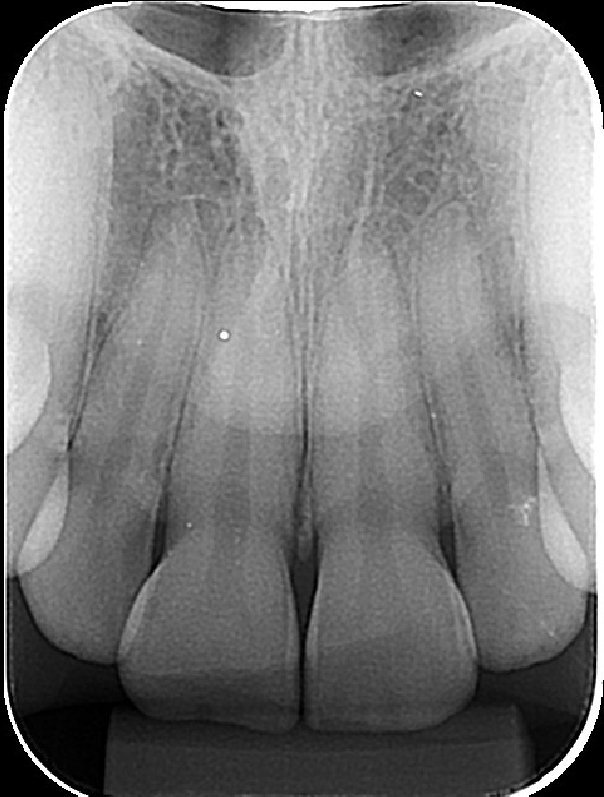

Periapical